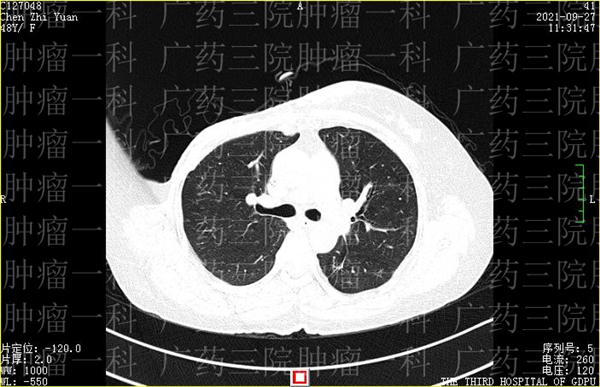

陈女士在2019年发现乳腺非特殊性浸润性癌后,进行了乳腺癌根治术。去年11月,陈女士在复查时,发现肿瘤出现了复发,为了控制病情,延长生命,她来到广药三院肿瘤一科,找到了彭齐荣教授。

经过会诊讨论,彭齐荣教授、刘跃军主任与诸位医生一起,为陈女士制定了微创灌注栓塞+增强免疫治疗方案。